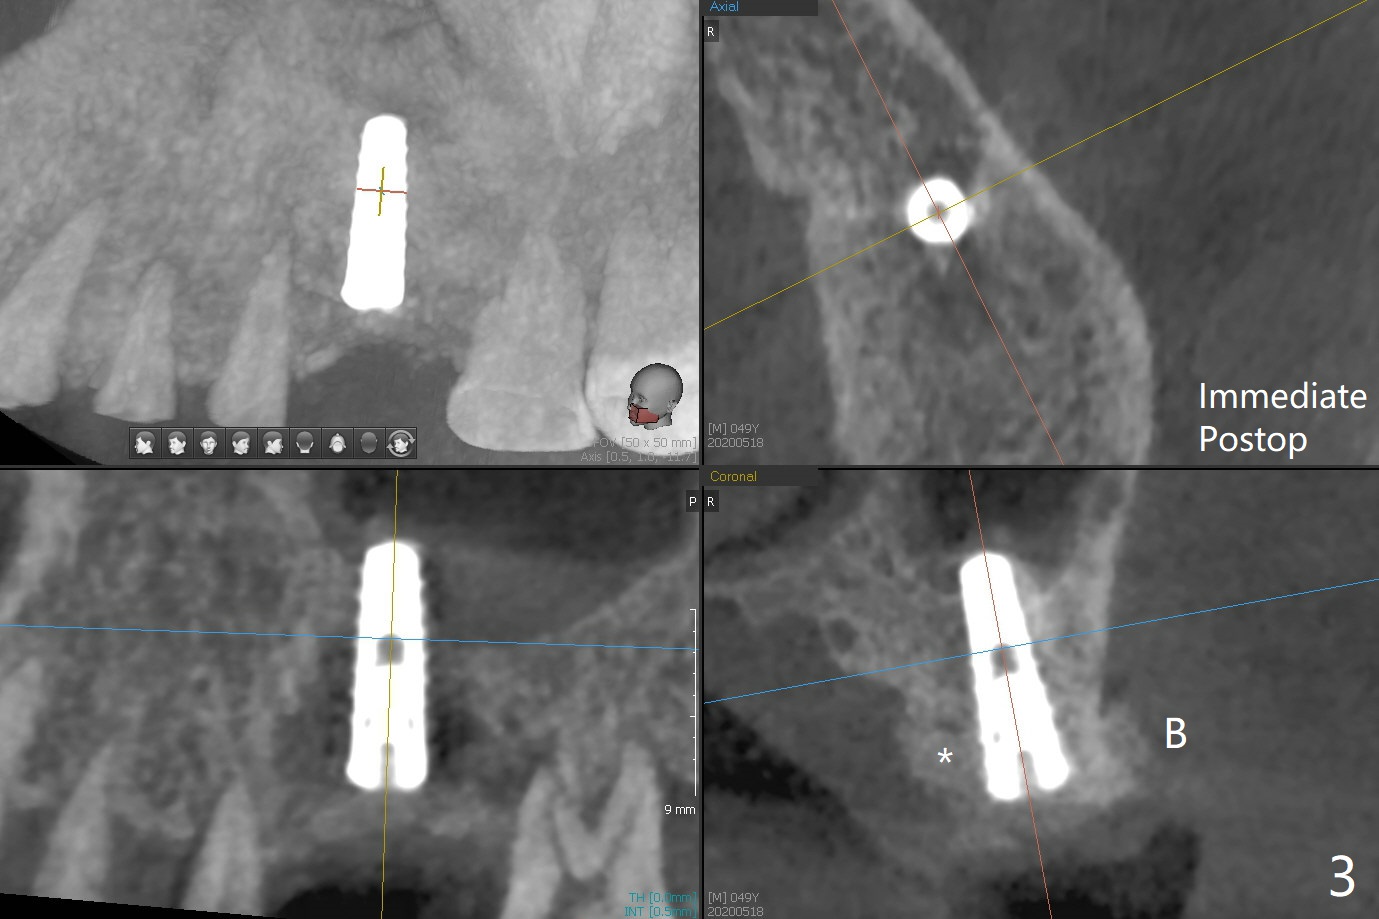

Nearly 4 months post implant exfoliation, the ridge at #14 looks narrow. Incision reveals loss of the palatal plate coronally. The same guide is used to finish osteotomy with modification. There are several points of difference. The 1st one is use of the guide for the complete procedure, including the implant placement so that there would be no apparent trajectory deviation. A bone-level implant is used instead of a tissue-level one. When a 4x11 mm dummy implant is ~1.5 mm shy of the depth (Fig.1 D), the palatal threads are exposed. To reduce further exposure, the final/definitive implant remains 4.0 mm in diameter instead of 4.5 mm as designed, followed by sticky bone, particularly palatal (Fig.2,3 *). In fact the implant is placed deeper than the failed one, relative to the sinus floor (Fig.4 (sinus lift without bone graft)). In fact the implant is placed deeper (Fig.4 (4x11 mm bone-level) than the failed one (Fig.5 (same magnification; 4.5x14 mm tissue-level)), relative to the sinus floor (yellow line).